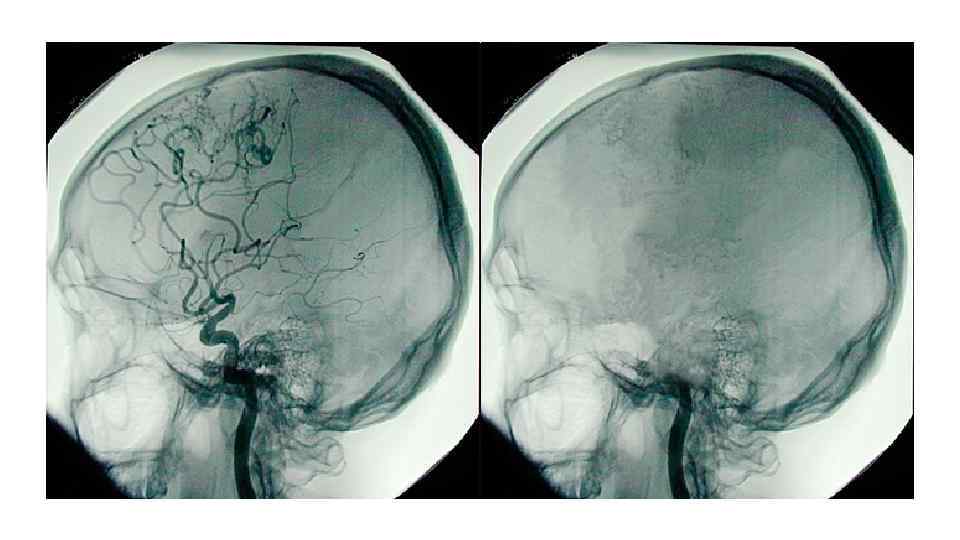

Инструментальные методы диагностики смерти мозга Исследование Комментарии 4 -х сосудистая панангиография Общих сонных и позвоночных артерий Золотой стандарт. Инвазивна, дорога КТ-контрастная цифровая субтракционная панангиография четырех магистральных сосудов головы Входит в российский стандарт диагностики. Та же степень специфичности и чувствительности, что и у ангиографии Однофотонная эмиссионная Весьма чувствительные и специфичные исследования. Альтернатива компьютерная томография (SPECT) ангиографии в Австралии. Дорого и не везде доступно и позитронная эмиссионная томография (PET) ЭЭГ Не способна выявить потенциалы со ствола мозга (слишком глубоко). Обязательна в некоторых европейских странах, рекомендована в США и России, не входит в австралийский алгоритм диагностики

Фотка • Ангиография 4 х сосудистая

Ангиография и PET-scan